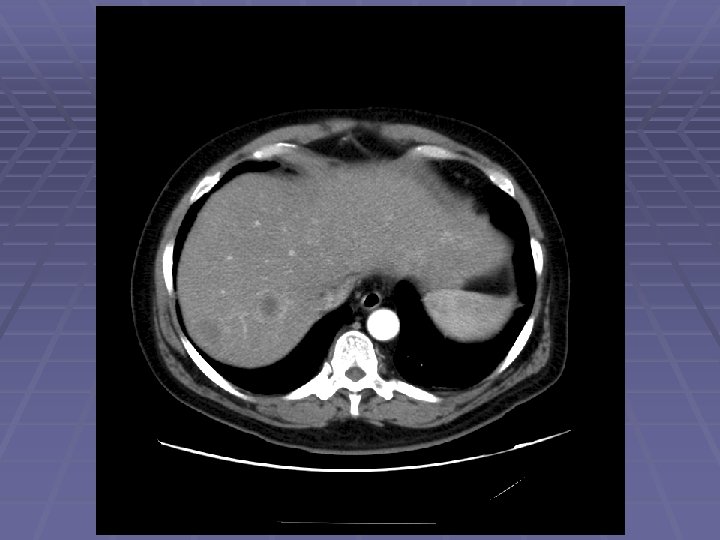

EUS Evaluation of Left Lobe of Liver